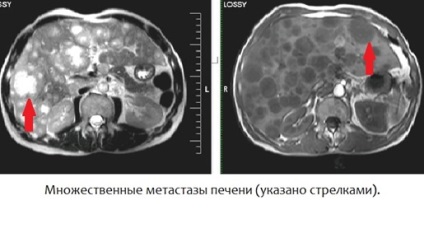

- Keresése áttétek diagnosztizálására és mértéke

Méretek definiálható ezzel a tanulmány formájában -. 1 cm együtt standard MRI tanulmány megbízhatóbb diagnózis Patológiai és az epevezeték, epehólyag halangiopankreatografiya használt. Ez lehetővé teszi, hogy azonosítsuk a kövek és struktúrák a lumen az epeutak és az epehólyag, valamint megbízhatóan diagnosztizálni anomáliák és szerzett szűkületet az epeutak. Használata kontraszt a leghasznosabb, ha a keresést és differenciáldiagnózisa között metasztázis, ciszták és hemangiomas.